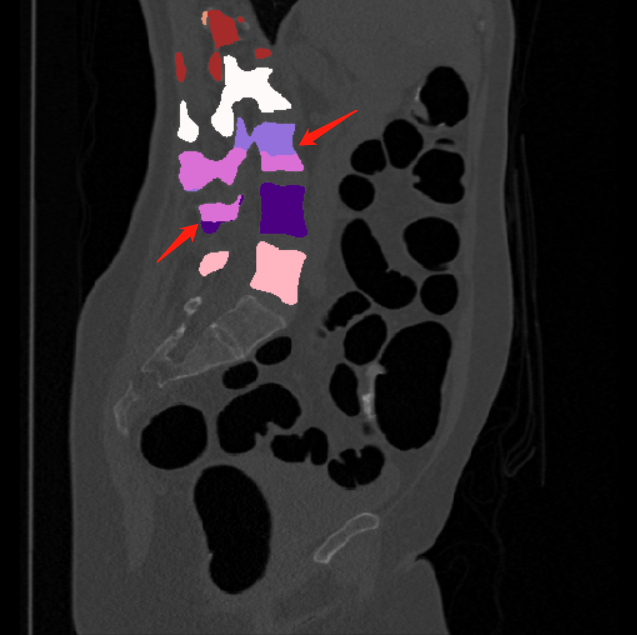

We calculate the two metrics of each vertebra, and the results are reported in Table 2. On the one hand, our experimental results are close to those reported in reference (Sekuboyina et al., 2020) with the same model (nnUnet), verifying the high quality of our annotations. On the other hand, Table 2 shows it is difficult to segment the diseased vertebrae (the DSC of L6 is almost 0). Specifically, the existence of L6 confuses the model, resulting in prediction dislocations (see the last row in Fig. 4). Thus, our labeled dataset, which contains many L6 cases, is very valuable for the diseased vertebrae segmentation (we have stated those cases that are hard for annotation in the readme.txt file). Table 2 illustrates that the model trained with our annotations can achieve good performance on our CTSpine1K dataset but a much worse performance on the VerSe Challenge datasets, which explains there is an obvious domain gap between our annotated dataset and the public dataset. We infer the reason is that the COlONOG dataset is based on an empty stomach and colon, confusing the deep learning model by the changes of air content in the abdomen (see Fig. 3). Therefore, our annotations are a good complement to the existing datasets.

Some visualization results are presented in Fig. 4, where we can observe that the baseline model can achieve excellent segmentation results. Nevertheless, some failed predictions occur when spinal diseases exist, especially sacral lumbarization and lumbar sacralization. Besides, the image’s resolution of Z direction is closely related to the results, and a lower resolution leads to worse results. Maintaining a reasonable performance for a low resolution is a research challenge. Image superresolution (Peng et al., 2020) might be worth exploring.